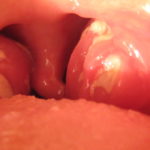

Обследуя горло, при этом заболевании, у детей будут замечены опухшие стороны гортани, где располагаются миндалины, при этом дыхание затруднено. Также могут быть зафиксированы единичные ранки на губах или многочисленные вокруг рта.

- появление бляшек и покраснений в гортани;